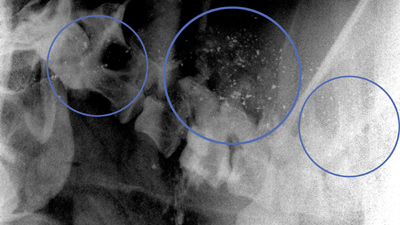

Michael Clark of the Los Angeles Zoo holding condor #79, Pitahsi during treatment for lead toxicity.

Michael Clark of the Los Angeles Zoo holding condor #79, Pitahsi during treatment for lead toxicity.Trailer & Additional video clips